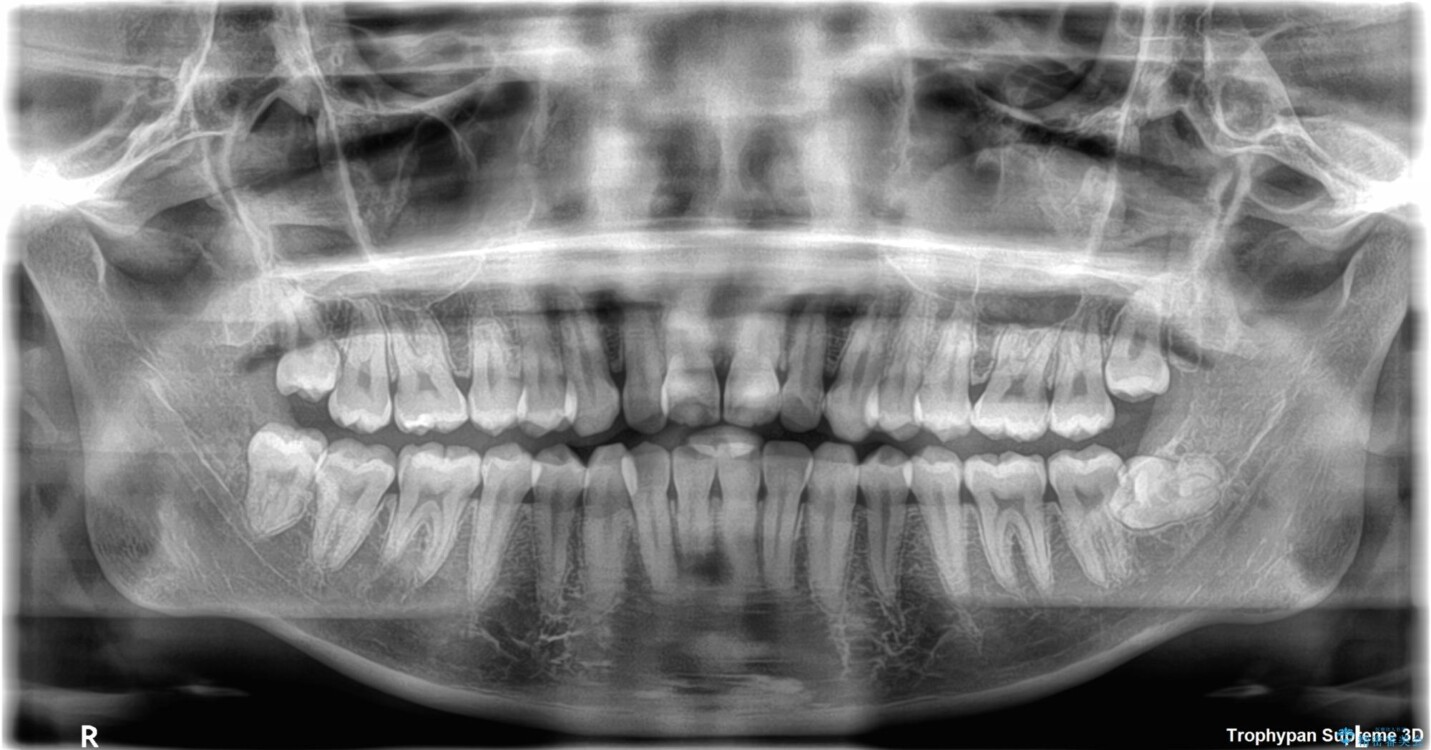

歯列アーチが狭くスペース不足により前歯がデコボコしている状態でした。見た目を改善しつつ、前歯を前方に突出させず、自然な笑顔を目指したいというご希望でした。

・アーチを側方に拡大して歯が並ぶスペースを確保

・抜歯は避け、非抜歯での対応

治療前

• 目立ちにくい表側装置で1年完了!狭いアーチを側方拡大し前歯のデコボコを整えた症例 治療前画像